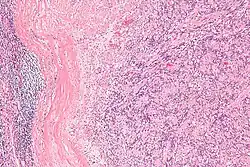

| Micrograph of an intranodal palisaded myofibroblastoma. H&E stain. | |

IPMs are diagnosed by examination of the tissue by a pathologist. They have a rim of peripheral lymphoid tissue (remnant of a lymph node) and consist of spindle cells with nuclear palisading. Red blood cell extravasation is common and blood vessels surrounded by collagen with (fine) peripheral spokes (amianthoid fibers) are usually seen.[2]

Immunostains for smooth muscle actin and cyclin D1 are characteristically positive. The main histologic differential diagnosis is schwannoma.